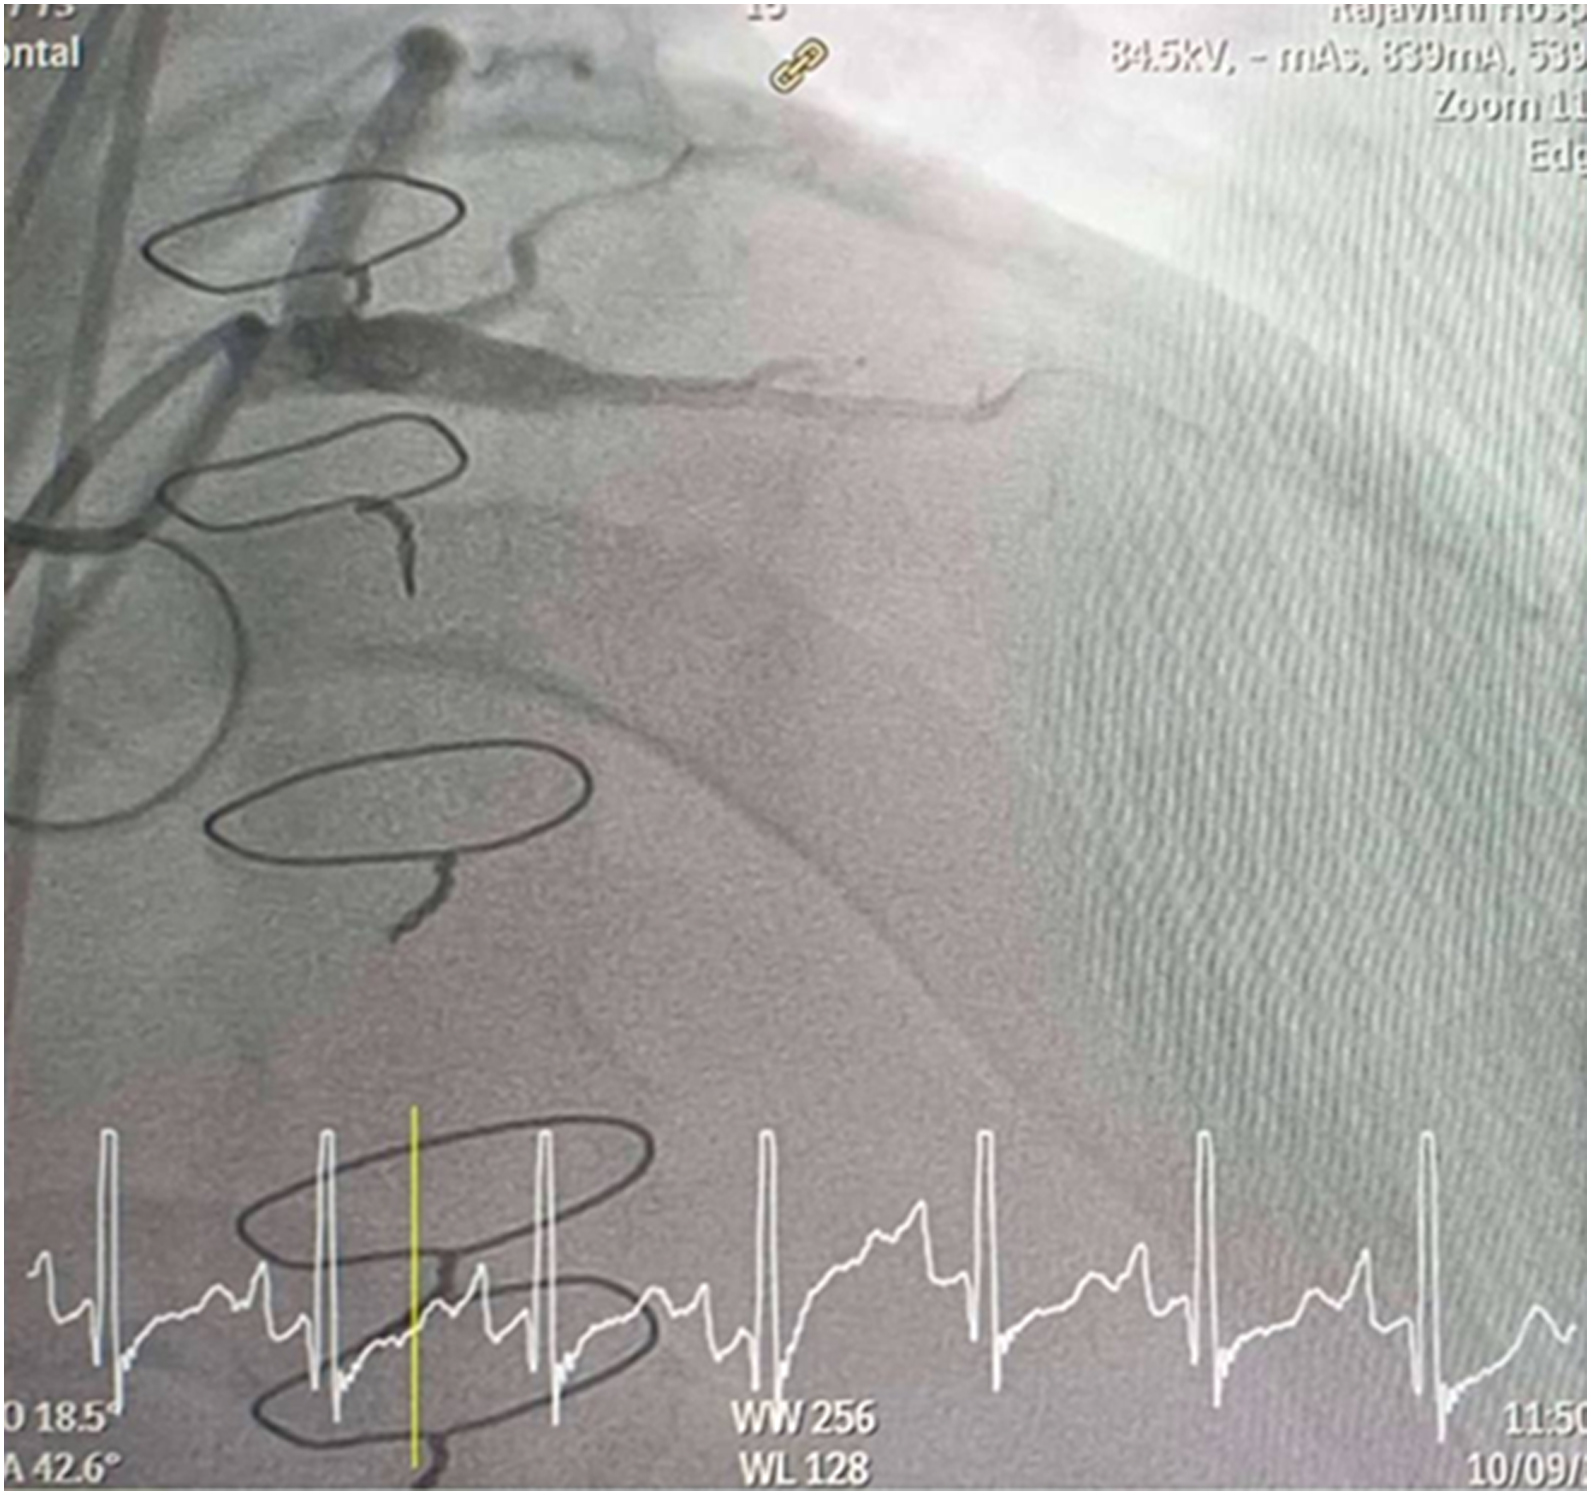

CAG was performed with right femoral approach with JL 4.0/7 Fr, JR 4.0/6 Fr diagnostic catheter showed

Right dominant

LM : mild irregular, non significant stenosis.

LAD : total occlusion mLAD.

LCx : mild irregular, non significant stenosis.

RCA : non significant stenosis.

Inserted Sion wire and thrombuster to LAD revealed multiple red clots.SC balloon 2.0 x 15 mm, then 2.5 x 15 mm, was inflated at mLAD up to 12 atm. IVUS insertion to LAD revealed vessels¡¯ size LM 5-5.5 mm, pLAD 4-4.5 mm, mLAD 3-3.5 mm with intraluminal thrombus, dLAD 2.75-3 mm. Multiple inflations were done at mLAD with SC balloon 2.5 x 15 mm. After multiple SC balloon inflations, the CAG revealed slow flow phenomenon. Then, the operator performed thrombus aspiration, multiple SC balloon 2.0 x 15 mm inflation and gave IC integrillin 3.4 ml. The final angiogram was acceptable result. The anticoagulant was given after CAG. Chest pain was subsided and hemodynamic parameters remained stable. EKG recorded after angiography showed resolution of ST elevation at V1-3. Later, the patient was discharged with warfarin. The Aortomitral intervalvular fibrosa repair surgery was planned due to embolic complication.